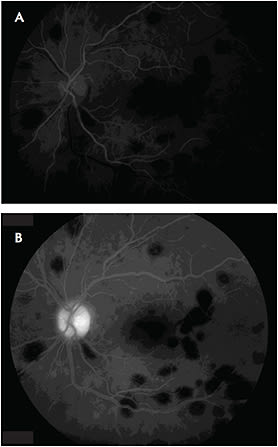

Fluorescein angiography demonstrated numerous punctate areas of hypofluorescence, consistent with blockage from the intraretinal hemorrhages (Figure 2). Spectral-domain OCT scans of the macula showed lesions within the inner retina corresponding to intraretinal hemorrhages but an otherwise unremarkable outer retina with an intact inner segment/outer segment junction and retinal pigment epithelium layer (Figure 3).

Figure 2. At presentation, fluorescein angiography of the left eye in both early (A) and late phases (B) showed good perfusion and hypofluorescence, corresponding to blockage from the intraretinal hemorrhage.